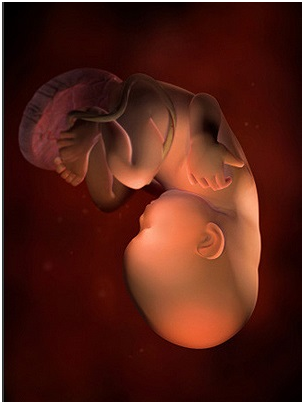

怀孕第28周胎儿图 从现在开始,你就进入了孕晚期,要注意的事情很多呦!你要每天做胎动...

怀孕第28周胎儿图 从现在开始,你就进入了孕晚期,要注意的事情很多呦!你要每天做胎动... -